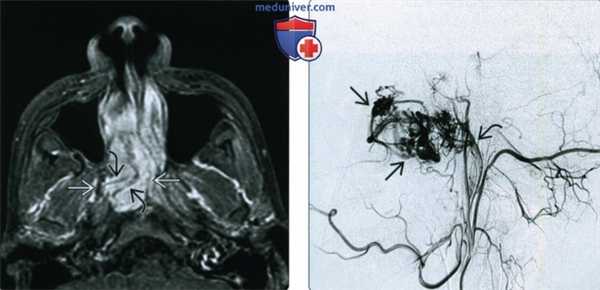

(Слева) При корональной костной КТ в полости носа и решетчатом лабиринте слева определяется экспансивное объемное образование. Обратите внимание на легкое ремоделирование окружающих костей, позволяющее сделать вывод о доброкачественности образования (шванномы), которое ошибочно может быть принято за мукоцеле.

(Справа) При аксиальной МРТ Т1 в полости носа справа определяется шваннома, смещающая носовую перегородку влево. В верхнечелюстной пазухе снаружи от образования находится «запертый» секрет с гиперинтенсивным сигналом.

4. МРТ при опухоли оболочки нервов пазухи, носа:

• Т1 ВИ:

о Типичный промежуточный сигнал

• Т2 ВИ:

о Гипо- или гиперинтенсивный сигнал ± интрамуральные кисты

• T1 BИ C+ FS:

о Шваннома: контрастное усиление в виде «водоворота»